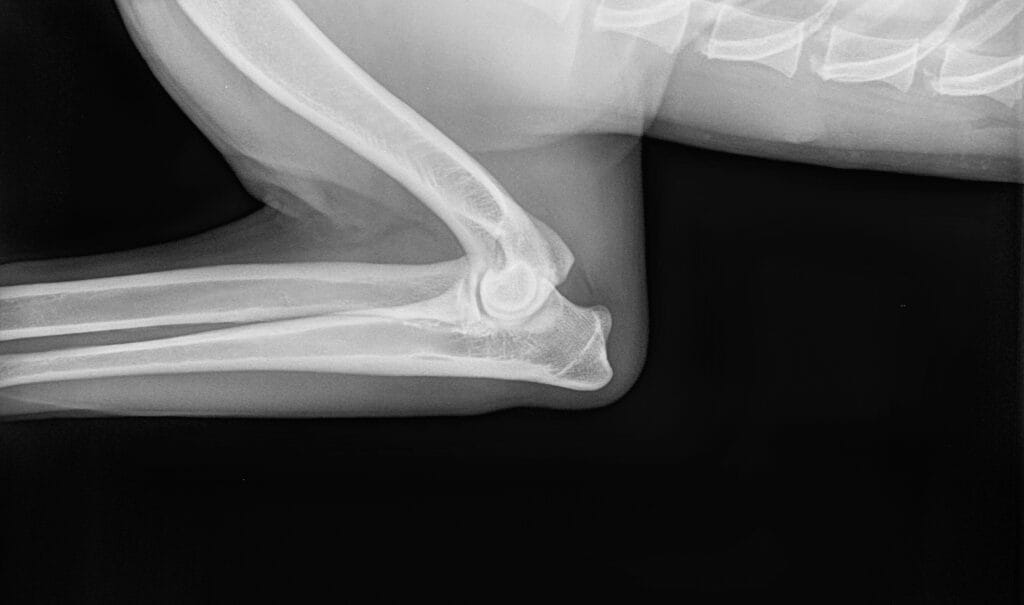

Other factors which can also be the cause of elbow dysplasia are osteochondrosis (OCD) which is a disease of the joint cartilage. OCD can be hereditary but it can also be the result of nutritional issues, such as over or under supplementation of certain vitamins and minerals, or trauma. Small fractures can also develop in the joint, leading ultimately to elbow dysplasia. These often go unnoticed if they are small hair-line fractures, or the dog is not exhibiting any major signs of discomfort.